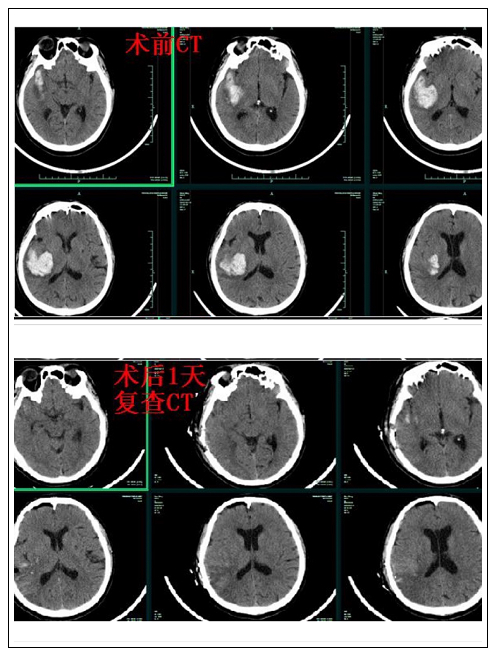

患者一:男性,63岁。因突发右侧基底节颞叶脑出血35ml,左侧肢体偏瘫(肌力1级)伴面瘫,口齿不清。颅内出血量较大,脑功能区受压明显,手术指征存在,急诊在神经外科行神经内镜微创手术清除血肿。术后第三天,左侧肌力即恢复至3级,术后8天(出院时)肌力恢复至4级。